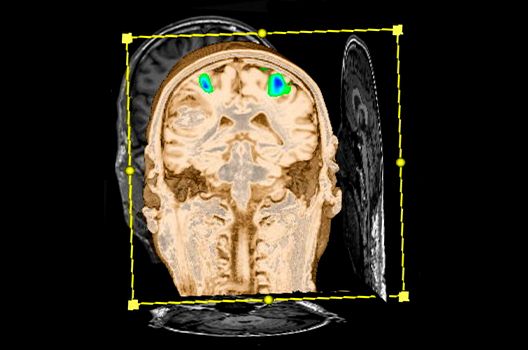

Die Magnetresonanztomographie (MRT) ist ein Verfahren, bei dem durch magnetische Kräfte Bilder des Körperinneren angefertigt werden. In der Neuroradiologie können manchmal kleinste Veränderungen schwere Folgen haben; daher forschen wir an der Entwicklung hochauflösender MRT-Sequenzen, mit denen diese Prozesse und auch einzelne Nervenfaserbahnen sichtbar gemacht werden können. Darüber hinaus sind bei vielen Erkrankungen des Gehirns die Blutgefäße betroffen. Daher arbeiten wir an der Neu- und Weiterentwicklung von MRT-Sequenzen zur Darstellung der Blutgefäße und zur Blutflussanalyse (sog. „Angio-MRT“). Einen besonderen Forschungsschwerpunkt unserer Klinik stellen die MR-Protonenspektroskopie und die funktionelle MRT dar, mit denen die Analyse einzelner chemischer Substanzen im Hirngewebe oder die Darstellung ausgewählter Hirnfunktionen möglich ist.

Die bildgebende Diagnostik und Verlaufsbeurteilung von Tumoren des Nervensystems ist einer der klinischen und Forschungsschwerpunkte unserer Abteilung. Eine besondere Bedeutung kommt der Hybrid-Bildgebung zu. Das Universitätsklinikum verfügt über einen integrierten Ganzkörper-PET/MRT-Scanner, der die Vorteile der MRT-Bildgebung und der Positronenemissionstherapie (PET) vereinigt. Aufgrund der langjährigen klinischen Arbeit und Forschungstätigkeit mit diesem Gerät hat die Neuroradiologie Tübingen maßgeblich zur Etablierung dieses Verfahrens beigetragen. Auch weiterhin forschen wir intensiv an neuen Methoden zur frühen Einordnung von Tumoren und insbesondere Tumorrezidiven, die mit anderen Methoden häufig nicht erfasst werden können.